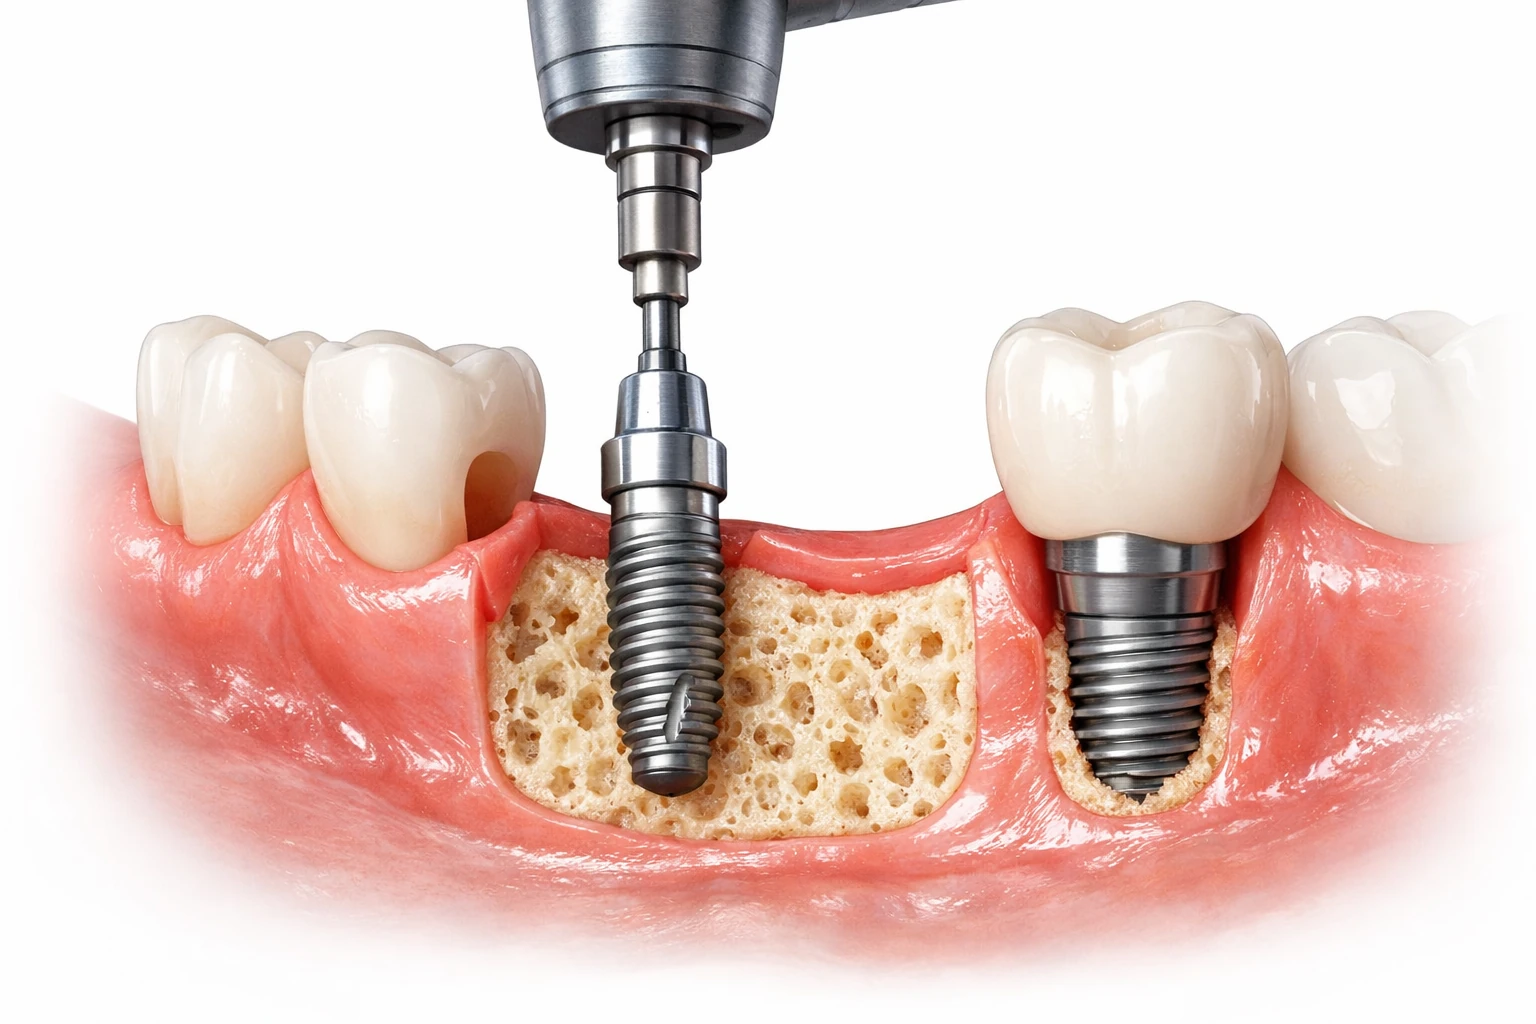

ایمپلنت فوری دندان یا ایمپلنت یکروزه به حالتی از کاشت گفته میشود که در همان جلسهای که دندان آسیبدیده کشیده میشود، پایه یا فیکسچر ایمپلنت در استخوان فک قرار میگیرد. برخی روشها حتی تاج موقتی را نیز در همان روز یا ظرف ۲۴–۴۸ ساعت بر روی ایمپلنت میگذارند تا بیمار بدون فاصله طولانی بدون دندان نباشد.

این در حالی است که در روش سنتی، پس از کشیدن دندان باید چندین هفته تا چند ماه صبر کرد تا استخوان و لثه بهبود یابد و سپس ایمپلنت کاشته شود، و پس از آن دوباره چند ماه برای ادغام استخوان و لثه منتظر ماند تا نهایتاً تاج دائمی نصب شود.

بررسی وضعیت استخوان فک، سلامت لثه و موقعیت دندان با تصویربرداری سهبعدی انجام میشود تا مشخص شود آیا فرد کاندید مناسبی برای ایمپلنت فوری هست یا خیر. - کشیدن دندان

دندان آسیبدیده ابتدا کشیده میشود؛ اگر پوسیدگی یا عفونتی وجود داشته باشد، این ناحیه پاکسازی میشود. - قرار دادن ایمپلنت

پایه ایمپلنت (فیکسچر) در همان روز در استخوان فک قرار میگیرد. سپس تاج موقت روی آن نصب میشود. - ادغام با استخوان (Osseointegration)

در ماههای بعدی، ایمپلنت با بافت استخوان جوش میخورد. در این دوره مراقبتهای ویژه و پیگیری دندانپزشکی اهمیت زیادی دارد.